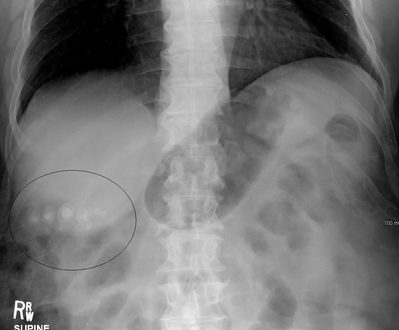

حصوات المرارة كما تظهر في الأشعة السينية العادية.